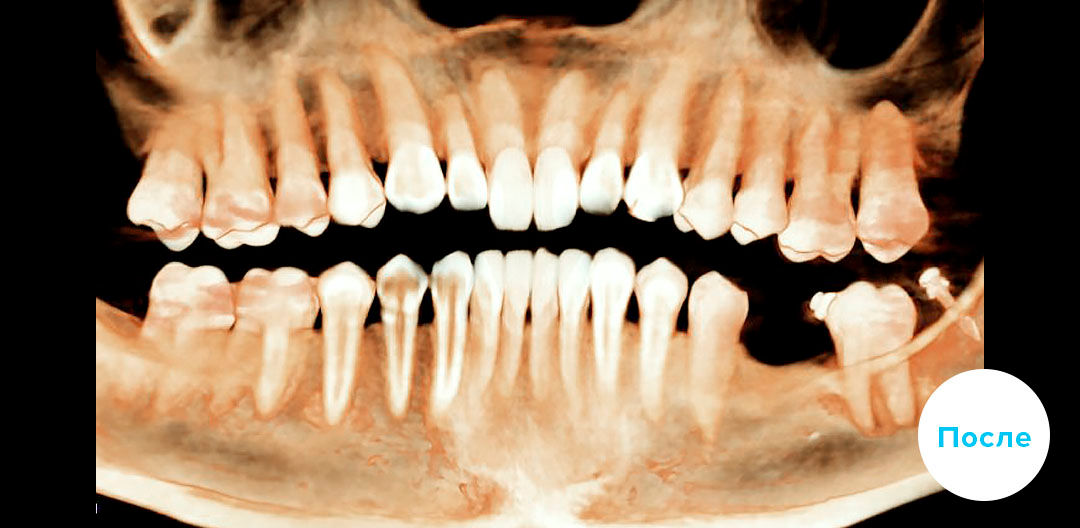

В приведенном клиническом случае ортодонты использовали мини-имплант и цепочки.